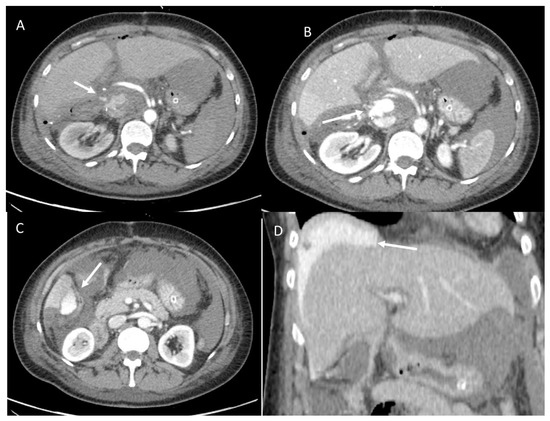

3.1.2. Posthepatectomy Hemorrhage

3.1.3. Vascular Thrombosis